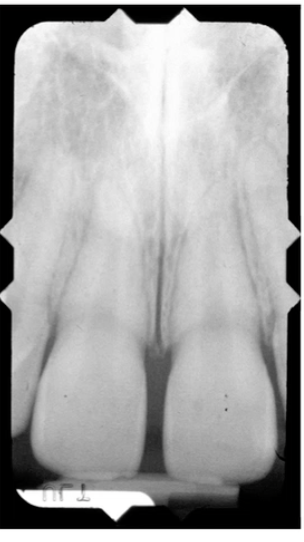

DENTAL ANATOMY

Dentine is of a lower density than enamel

Teeth sit in the alveolar bone, are separated from the bone by pdl

High density enamel- radiopaque and white around the outside

Slightly lower density dentine-smooth grey

Root canal- soft tissue compared to enamel- doesn’t attenuate x rays as much- hence radiolucent(black) appearance

Black outline around tooth is the pdl space and next to it is a white line which is the bone. This is cortical bone, which is more dense than the cancellous bone seen between the teeth

Maxillary central incisors- enamel is thinner on incisors compared to molars, broader canal and a single conical root